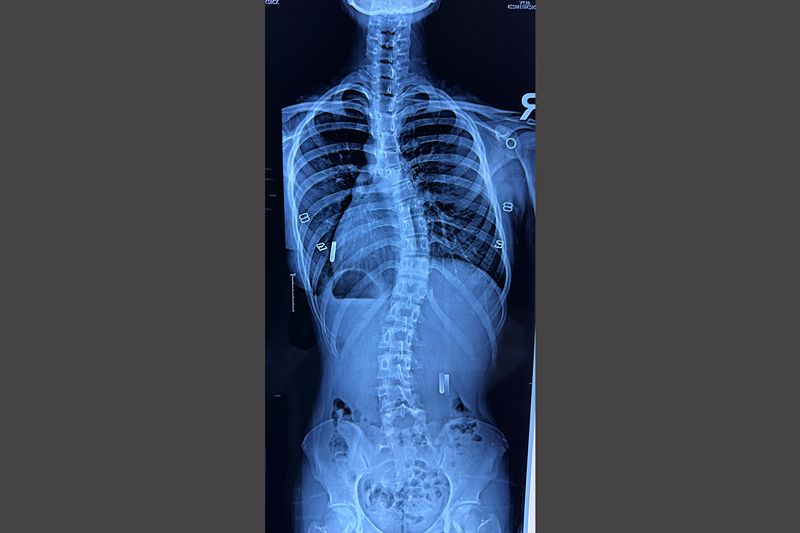

脊柱侧弯隐匿性较强,但会随年龄的增长而逐渐加重。其主要表现为躯干歪斜,脊柱骨骼呈“S”型,后背部有“大包”,“大包”在弯腰时更加明显,双侧肩膀不等高,身高缩水等,进而影响身体平衡,导致肺组织受压、生长发育迟缓、寿命大大缩短以及心理问题等。

“早治疗”方能对症下药。尽管脊柱侧弯的主要人群是8-15岁的中小学生,但幼儿家长同样也不能掉以轻心。脊柱侧弯如能早期发现、及时治疗,绝大多数不需要进行手术,定期到脊柱侧弯专科门诊检查,通过形体训练、正规硬质支具治疗、强化康复等保守治疗方式即可矫正,扼杀侧弯“萌芽”。